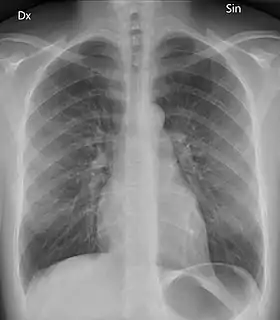

Chest

A normal posteroanterior (PA) chest radiograph.

Chest radiographs are used to diagnose many conditions involving the chest wall, including its bones, and also structures contained within the thoracic cavity including the lungs, heart, and great vessels. Conditions commonly identified by chest radiography include pneumonia, pneumothorax, interstitial lung disease, heart failure, bone fracture and hiatal hernia. Typically an erect postero-anterior (PA) projection is the preferred projection. Chest radiographs are also used to screen for job-related lung disease in industries such as mining where workers are exposed to dust.[12]

For some conditions of the chest, radiography is good for screening but poor for diagnosis. When a condition is suspected based on chest radiography, additional imaging of the chest can be obtained to definitively diagnose the condition or to provide evidence in favor of the diagnosis suggested by initial chest radiography. Unless a fractured rib is suspected of being displaced, and therefore likely to cause damage to the lungs and other tissue structures, an X-ray of the chest is not necessary as it will not alter patient management.